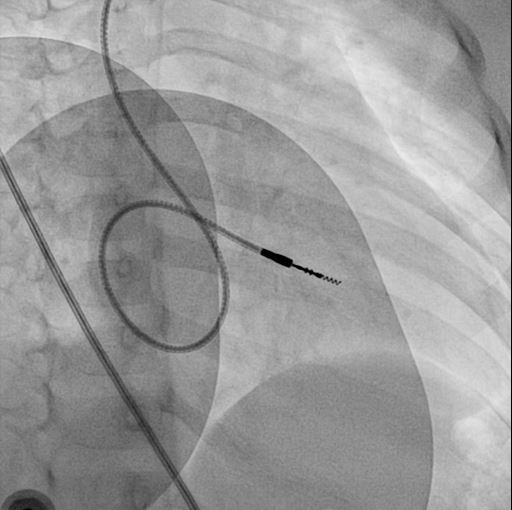

Extra loop

alpha_loop.jpg